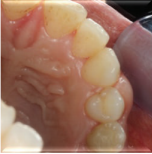

计划切除增生牙龈。由于增生范围较大,拟利用腭侧牙龈进行软组织修复。

患者1月、6月、12月后复诊,恢复良好,无复发。 牙龈纤维瘤在临床属于较常见疾病,多采用手术切除方式,注意要与其他类型牙龈增生相鉴别。手术切除纤维瘤后,若缺损较大,尤其实在美学区,影响美观,可以利用周围皮瓣进行修复。术后菌斑控制也很重要。